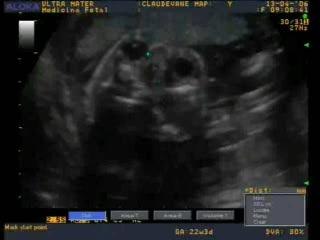

Ecografia Ostetrica 20 settimane